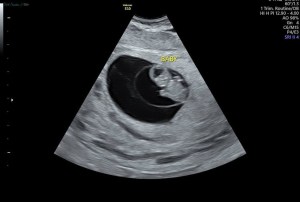

If you came here for the ultrasound pics, I promise I won’t disappoint! We’ve had a few ultrasounds already, so here are our favorite images from our 8 week, 10 week, and 12 week ultrasounds.